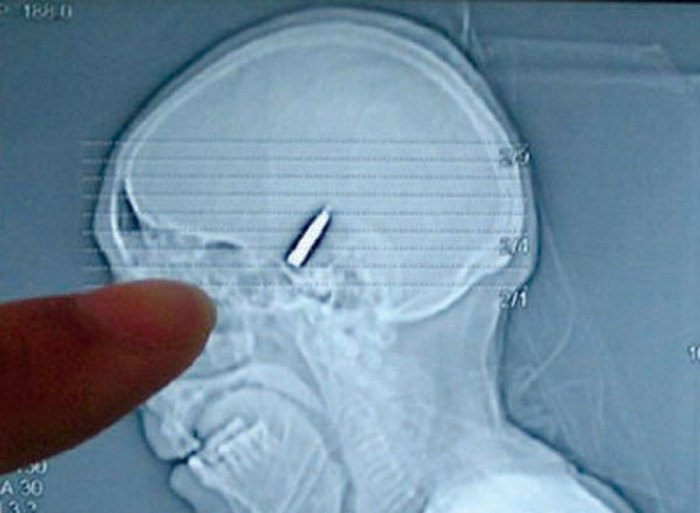

8. С пулей в голове

С пулей в голове.

В 2007 году мужчина во Флориде проснулся с сильной головной болью. Он пошел в больницу, где врачи обнаружили пулю в его мозгу. Его жена позже призналась, что случайно выстрелила в него.